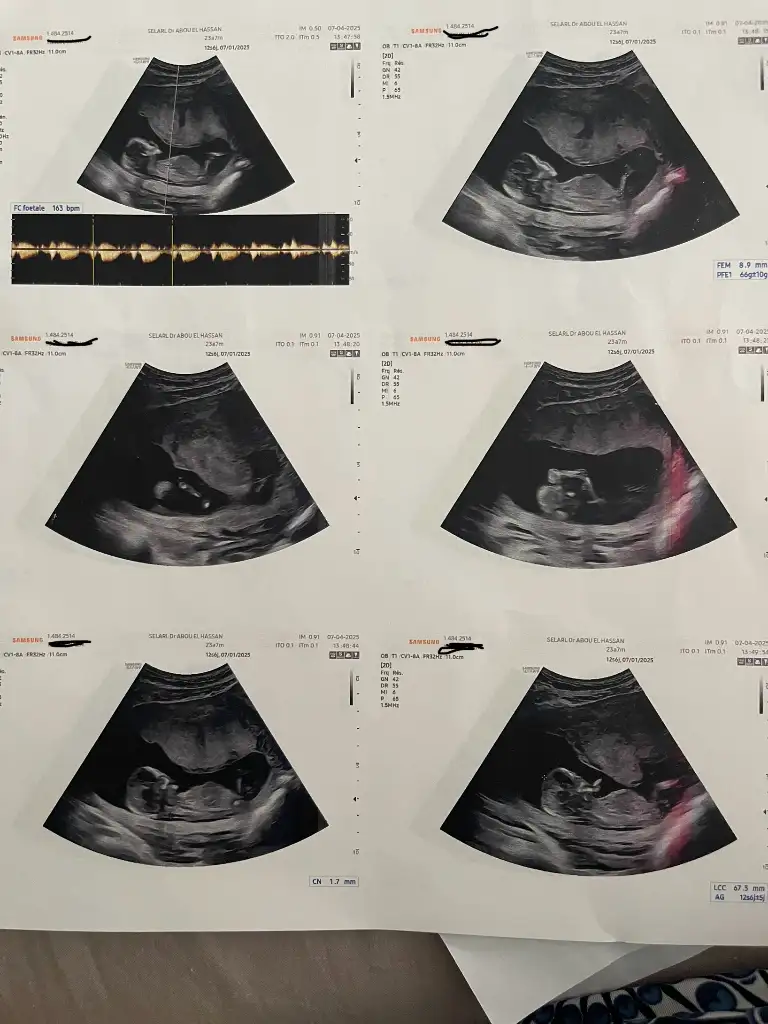

Banada bakarmısınız lütfenn

13 haftalık sizce cinsiyeti nedir